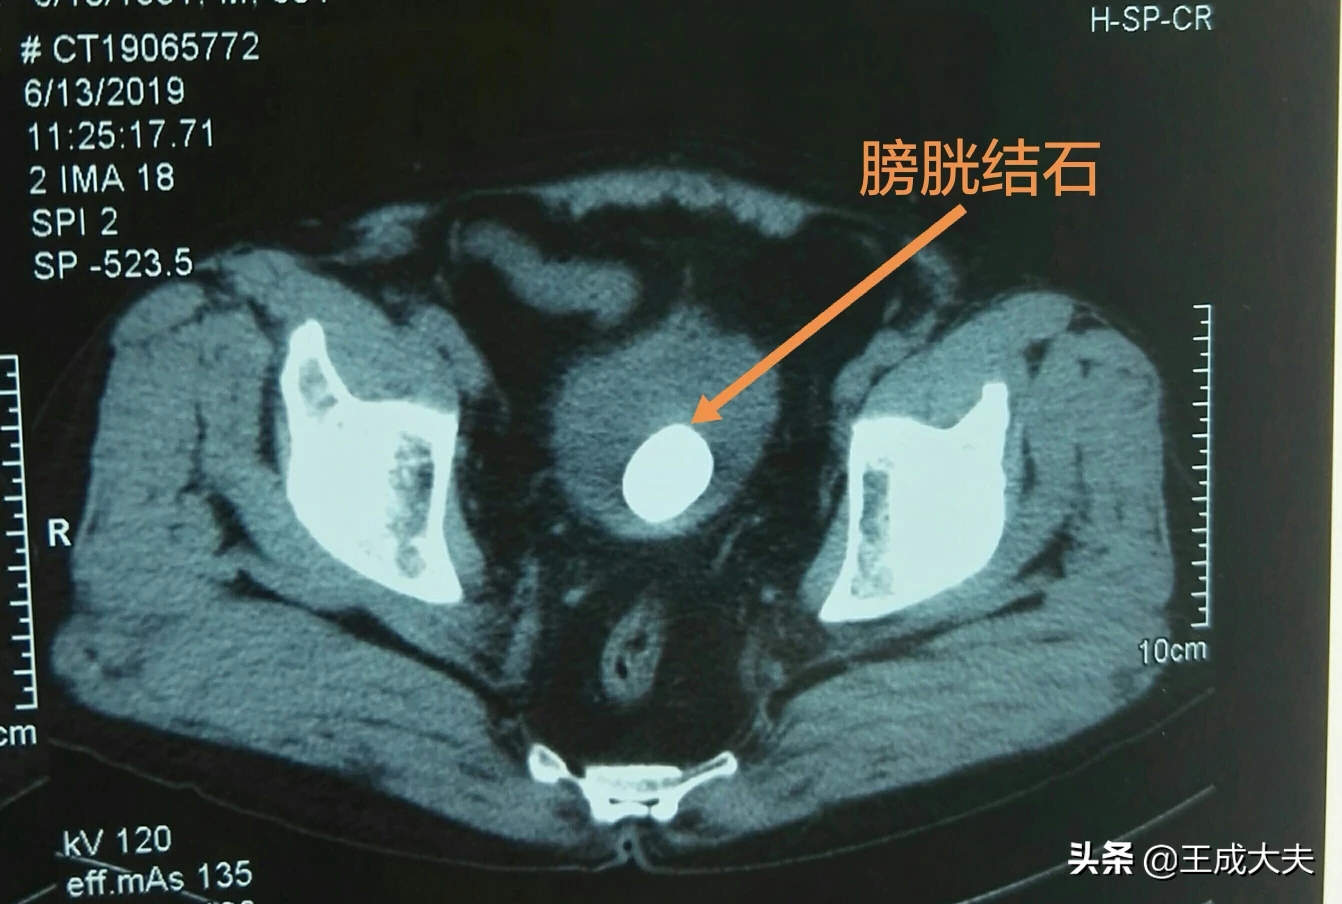

文章插图

长时间放置尿管容易出现膀胱结石